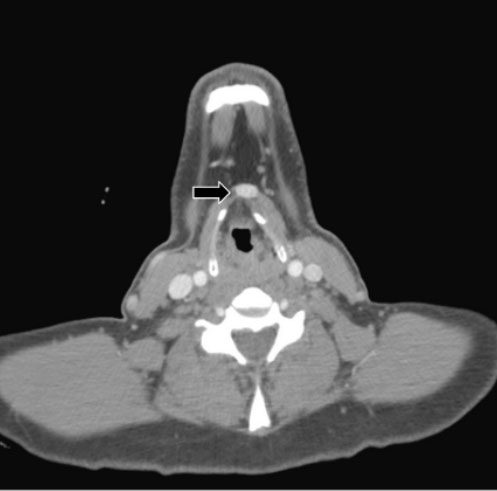

A 46-year-old male with a past medical history of hypothyroidism and cannabis use disorder presented to his primary care physician with a globus sensation and left cervical lymphadenopathy for two weeks. A computed tomography (CT) scan of the neck with contrast identified three high attenuation areas: the first in the midline floor of the mouth extending posteriorly to the base of the tongue (1.5 × 2.2 cm) (Figure 1), the second at the base of the tongue (1.4 × 1.8 × 3.0 cm) (Figure 2), and the third in the midline of the neck just beneath the hyoid bone (1.3 cm) (Figure 3). Thyroid tissue was not identified in the orthotopic location (Figure 4). A follow-up thyroid uptake and scan confirmed that each of these high attenuation areas was also iodine avid, consistent with thyroid tissue (Figure 5). Notably, there was no uptake in the normal orthotopic thyroid location.

Figure 2: Ectopic thyroid tissue located at the base of the tongue (1.4 × 1.8 × 3.0 cm).

In the reported cases of triple ectopic thyroid, the most common locations were the lingual (88%) and suprahyoid (88%) regions [1],[2],[3],[4],[5],[6],[7]. Less common locations included the infrahyoid (50%), pre-tracheal (25%), and cricoid cartilage (13%) areas [1],[2],[3],[4],[5],[6],[7]. Lastly, one patient only had ectopic thyroid lateral to the orthotopic thyroid [8]. In addition to lingual (Figure 1) and infrahyoid (Figure 2) areas, our patient had ectopic thyroid in the midline mouth (Figure 3) which has not previously been described and would seem quite unusual given the embryological pathway in normal thyroid development.